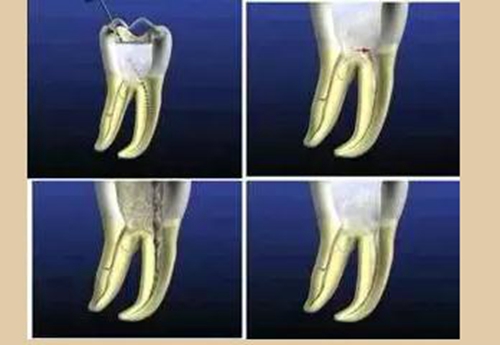

二、根管預(yù)備后形態(tài)

牙體缺損的修復(fù)需要將剩余牙體組織制備成一定形態(tài),以利修復(fù)體的良好固位。根管充填為了致密封閉根管系統(tǒng)也需要良好的根管預(yù)備后形態(tài)。

常規(guī)概念的根管預(yù)備后形態(tài)有: ( 1 )便宜形態(tài)( convenience form )。 ( 2 )保持形態(tài)( retention form )。

常規(guī)概念的根管預(yù)備后形態(tài)有:

( 1 )便宜形態(tài)( convenience form )。

( 2 )保持形態(tài)( retention form )

( 3 )抵抗形態(tài)( resistance form )。

1. 便宜形態(tài)

便宜形態(tài)是自切端或咬頜面朝向根尖的直線開(kāi)擴(kuò)尖錐形態(tài),減少污染物推出根尖孔,方便沖洗、根管充填和側(cè)壁施壓。

2. 保持形態(tài)

保持形態(tài)是根尖狹窄部?jī)?nèi) 1 — 2mm 的一段距離,由擴(kuò)大器回轉(zhuǎn)切割而不貼根管壁提拉切割制成,是擴(kuò)大器的原始形態(tài)(近似平行)。在測(cè)試主牙膠尖時(shí)給測(cè)試者有一個(gè)牽引抵抗 (tugback) 的感覺(jué)。

3. 抵抗形態(tài)

抵抗形態(tài)是根管預(yù)備的根尖形態(tài),它是由擴(kuò)大器或根管銼尖端 75 度角自然切割而成。其目的是防止根管充填材超出根尖孔,并且使根尖封閉更加嚴(yán)密。